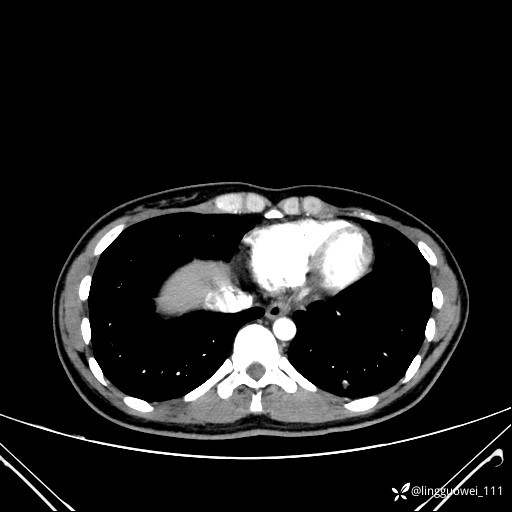

患者性别:女

患者年龄:26岁

主诉:咳嗽来诊,结节性质不明。

肺毛细血管瘤 (2)